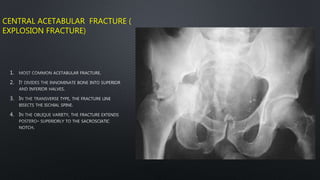

CENTRAL ACETABULAR FRACTURE (

EXPLOSION FRACTURE)